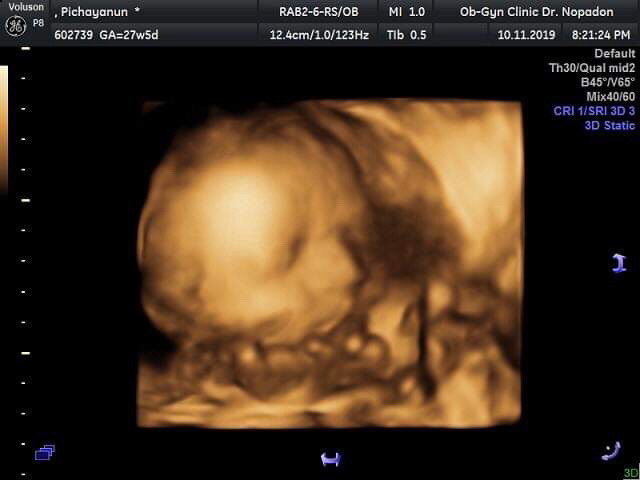

ผู้หญิงค่ะ